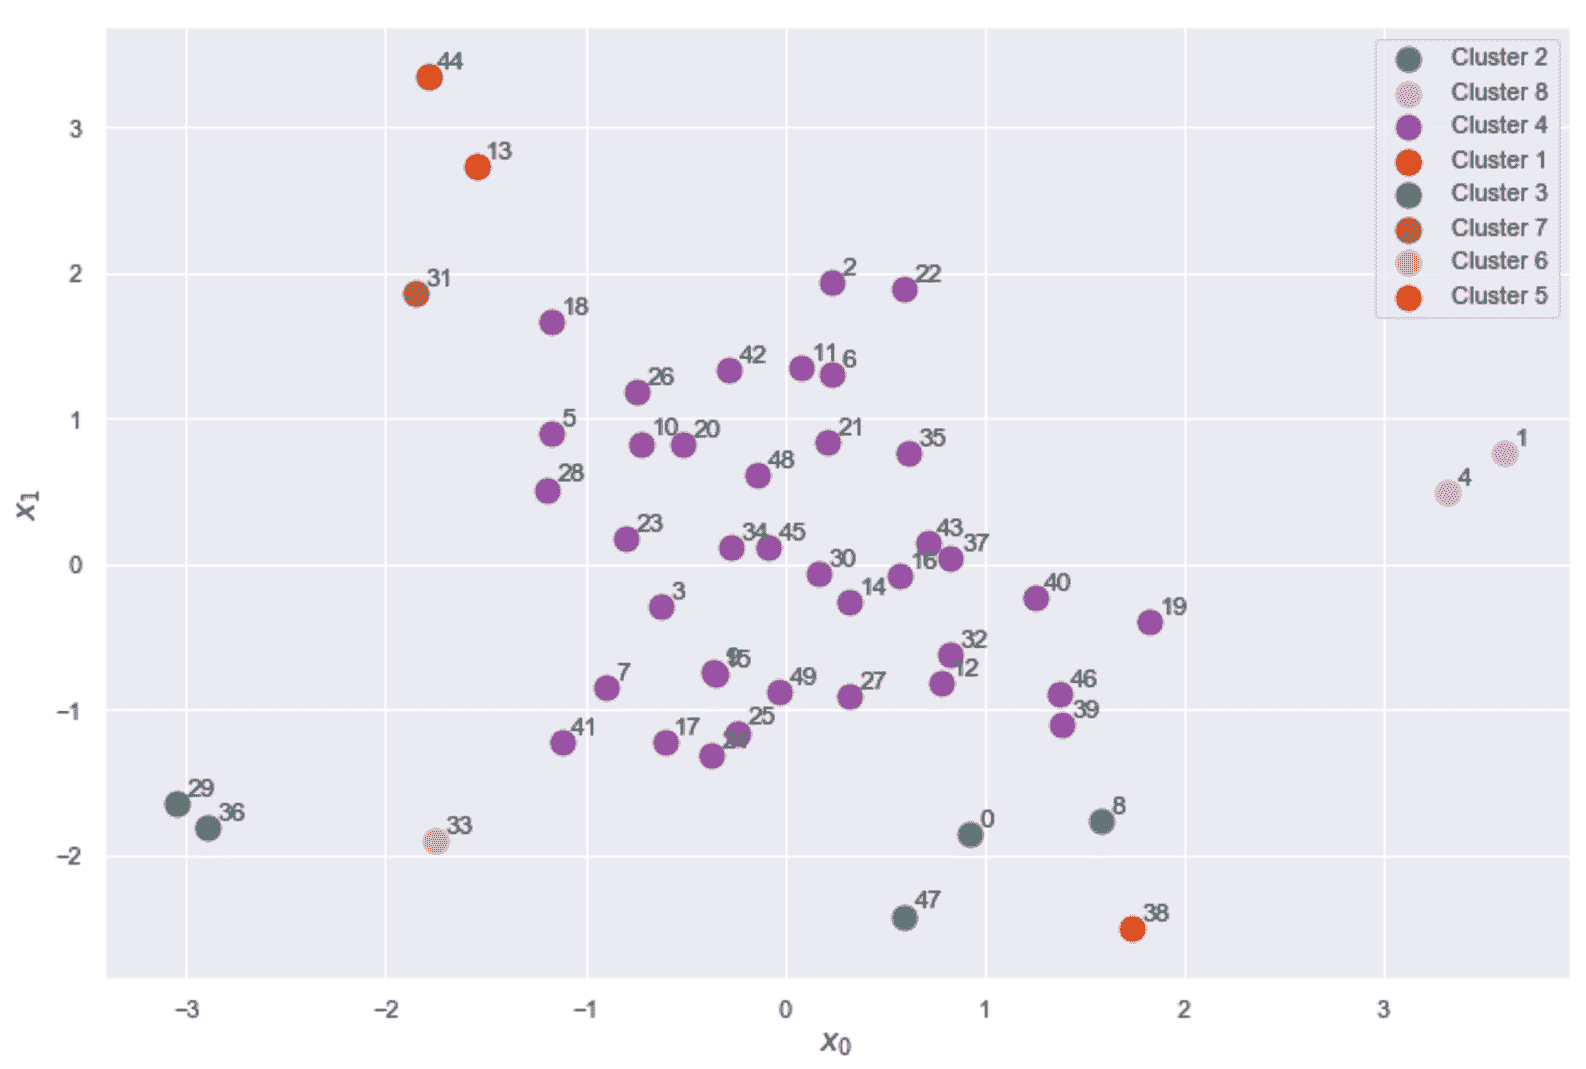

生成的绘图显示在以下屏幕截图中:

乳腺癌威斯康星州数据集的 K 均值聚类(K = 8)结果

现在,让我们考虑位于图底部的子群集(-25 < x < 30和-60 < y < -40) , 如下:

乳腺癌威斯康星州数据集的轮廓图

第一张图显示了K = 2的自然聚类。 第一个轮廓非常清晰,表明平均群集间距离具有较大的差异。 而且,一个集群比另一个集群具有更多的分配(即使它不那么尖锐)。 从数据集描述中,我们知道这两个类别是不平衡的(357 良性与 212 恶性),因此,不对称是部分合理的。 但是,一般而言,当数据集平衡时,良好的轮廓图的特征是具有均匀轮廓的均质群集,其圆形轮廓应接近 1.0。 实际上,当形状类似于长雪茄时,这意味着群集内距离非常接近其平均值(高内聚),并且相邻群集之间存在明显的分隔。 对于K = 2,我们拥有合理的分数,因为第一个群集达到 0.6,而第二个群集具有约 0.8 的峰值。 但是,尽管后者的大多数样本的特征是s(•) > 0.75,但在前一种样本中,约有一半的样本低于 0.5。 分析表明,较大的聚类更均匀,并且 K 均值更易于分配样本(即,就度量而言,x[i] ∈ K[2]的方差较小,在高维空间中,代表K[2]的球比代表K[1]的球更均匀。)。

其他图显示了类似的情况,因为已检测到非常紧密的聚类以及一些尖锐的聚类。 这意味着宽度差异非常一致。 但是,随着K的增加,由于分配的样本数趋于变得相似,因此我们获得了更加均一的群集。 具有s(·) > 0.75的非常圆形(几乎矩形)的群集的存在证实了数据集至少包含一组非常有凝聚力的样本,相对于分配给其他群集的任何其他点的距离都非常接近。 我们知道,恶性类(即使其基数更大)更为紧凑,而良性类则分布在更宽的子空间中。 因此,我们可以假设,对于所有K来说,最圆的群集是由恶性样本组成的,而其他所有群集都可以根据其清晰度进行区分。 例如,对于K = 8,第三群集很可能对应于第一图中第二群集的中心部分,而较小的群集包含属于良性子集的孤立区域的样本。

如果我们不了解基本事实,则应同时考虑K = 2和K = 8(甚至更大)。 实际上,在第一种情况下,我们可能会丢失许多细粒度的信息,但是我们正在确定一个强大的细分领域(假设由于问题的性质,一个集群的凝聚力不是很高)。 另一方面,在K > 8的情况下,群集明显更小,具有适度的内聚性,它们代表具有某些共同特征的亚组。 正如我们在上一节中讨论的那样,最终的选择取决于许多因素,这些工具只能提供一般的指示。 此外,当聚类是非凸的或它们的方差未在所有特征之间均匀分布时,K 均值将始终产生次优表现,因为所得聚类将包含较大的空白空间。 如果没有特定的方向,则群集的最佳数量与包含均匀(宽度大致相同)的圆形图的图相关联。 如果形状对于任何K值仍然保持清晰,则意味着几何形状与对称度量不完全兼容(例如,群集非常拉伸),应考虑其他方法。